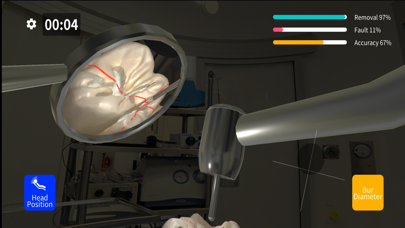

Скриншоты